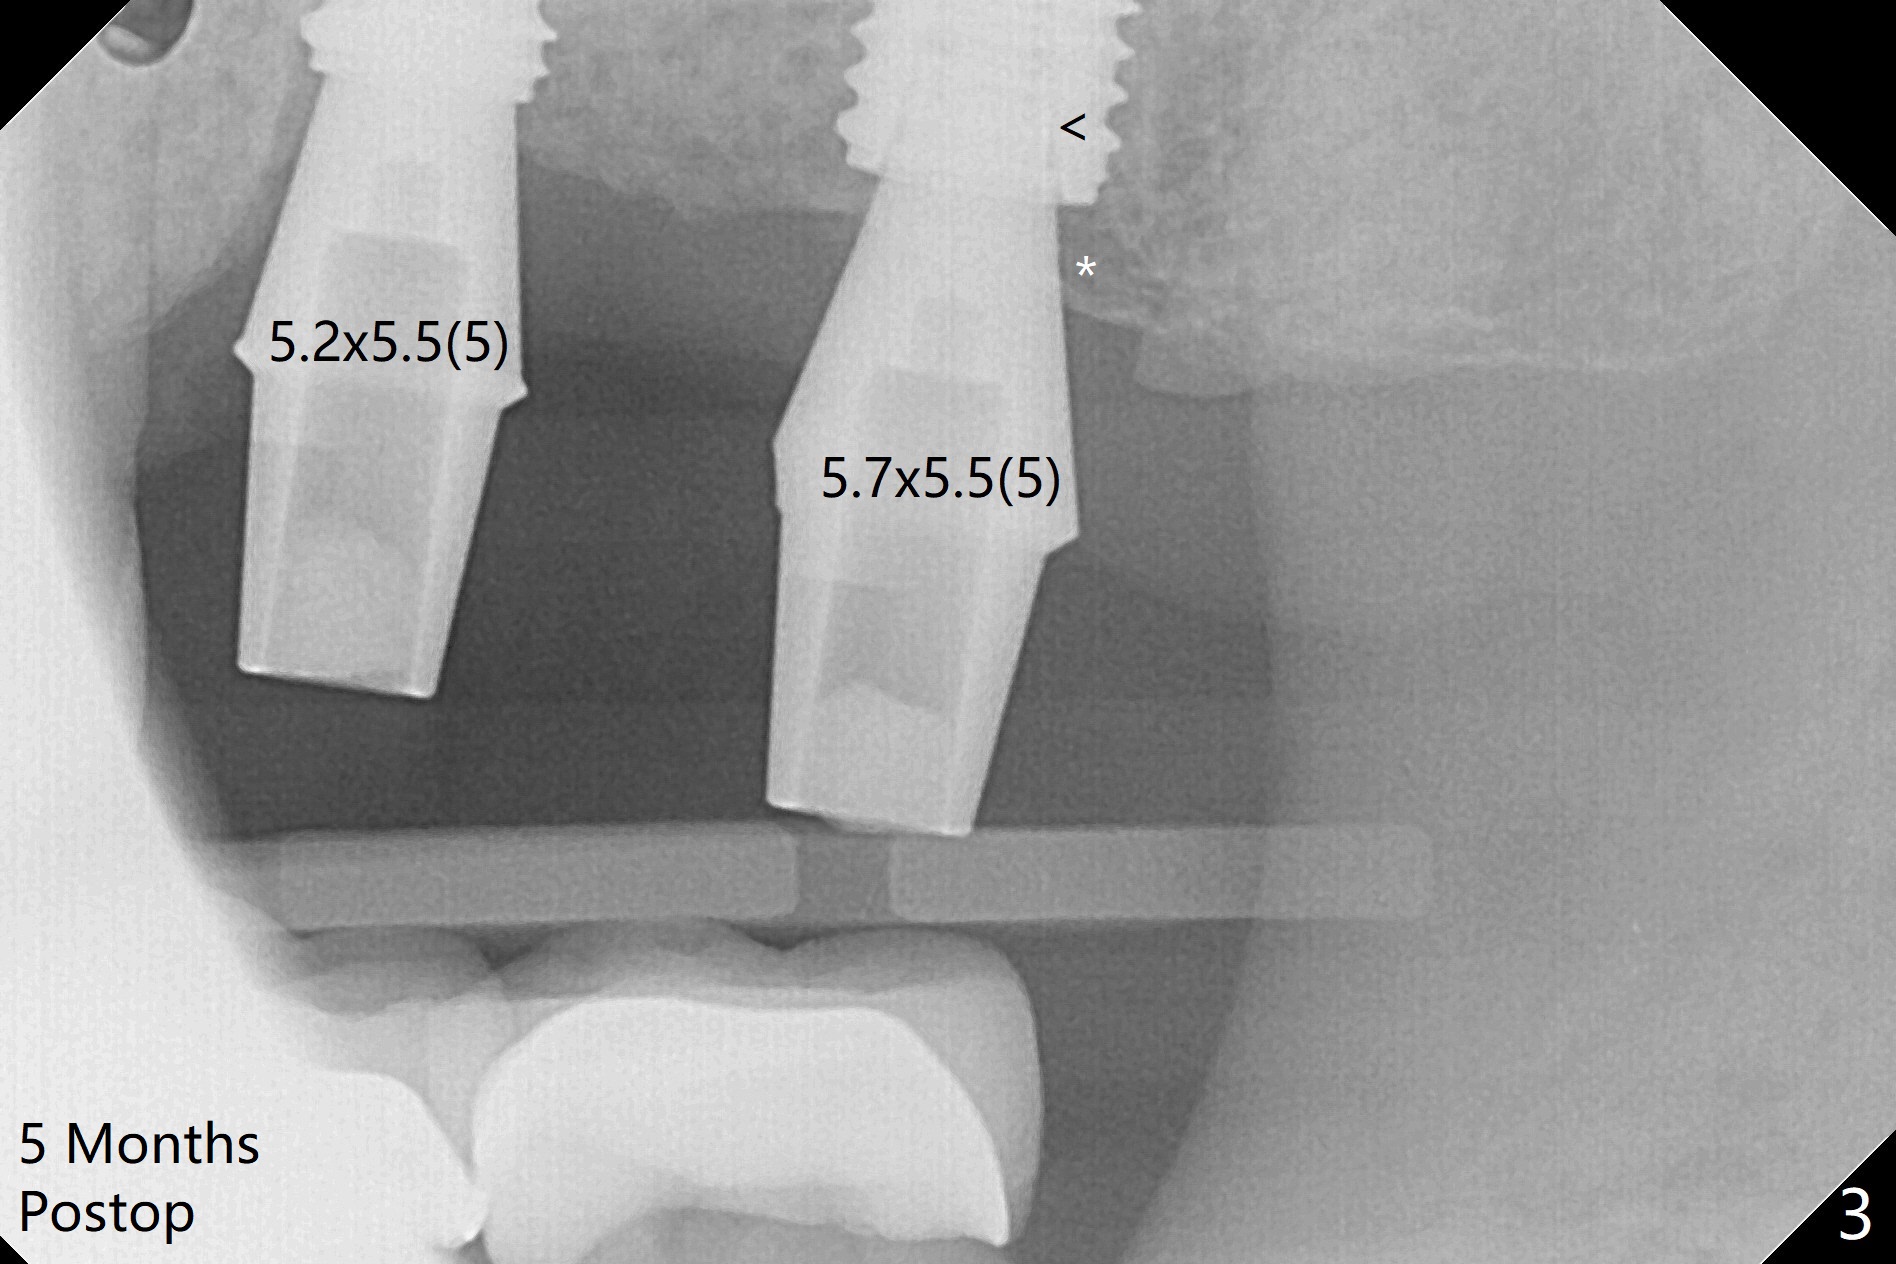

With one carpule of 2% Xylocaine with 1:100,000 Epinephrine, there is no intraop pain associated with placement of 2 implants with guide (Fig.1). Postop pain is minimal. Difficulty is high torque in insertion. At the site of #15, there is no bone shaving associated with 4 mm or less drills. The deeper portion of the bone seems to have denser bone. In spite of using 5 mm tap, which is not recommended, the insertion torque is so high that the implant has to be backed up several times before placement with ~ 50 Ncm. Bone profile is used at #14 before placement of a 5.5x7 mm healing abutment. The healing abutment at #15 dislodges 3 weeks postop and changes to a 5.5x5 mm one. No bone loss is observed 4 months postop (Fig.2). After failure to deliver crowns using impression coping, abutments are placed. The one at #15 is incompletely seated (Fig.3 <) probably due to the contact with the distal crest (*). Change to a smaller one results in complete seating (Fig.4). Cementation of the crowns with access holes is related to no residual cement (Fig.5).